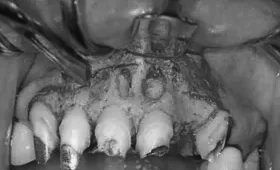

• 治療前

• 治療後

歯根端切除術

根管治療が不十分な場合、歯根の先端に膿の袋(歯根嚢胞)が形成されることがあります

膿の袋が大きすぎる場合は抜歯が必要になりますが、そうでなければ外科的に根の先端を切除し、同時に膿の袋を取り除く処置を行います。